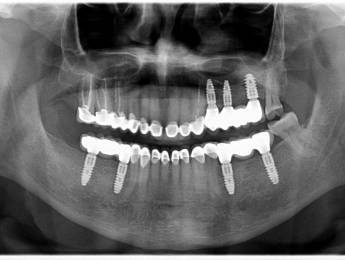

1. eset

A páciens fogágybetegség miatt érkezett hozzánk. A felső fogak menthetetlen állapotban voltak. All on 6 megoldásként a felső fogak eltávolításakor 6 implantátum került beültetésre és a páciens azonnal egy fix ideiglenes hidat kapott. 4 hónapos gyógyulási idő után készült el a felső fémkerámia leplezésű körhíd.